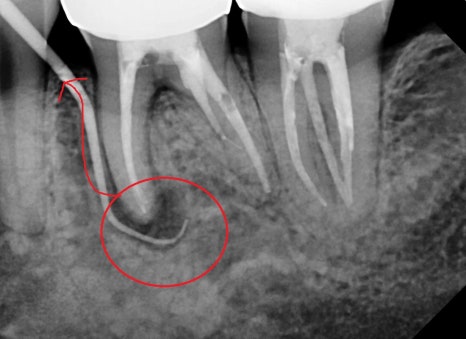

좌측 사진은 잇몸에 고름주머니가 생긴 증상이고,

이것은 뿌리 쪽 염증이 바깥 뼈를 녹이며 외부로

노출이 된 상태이며

이것을 확인하기 위해 고름주머니를 통해

염증의 근원지가 어디인지 엑스레이를 통해 알아보았습니다.

신경치료가 된지 상당히 시간이 지나서

어려움이 예상되긴 하지만

발치한 마지막으로 재신경치료를 시도하기로 했습니다.